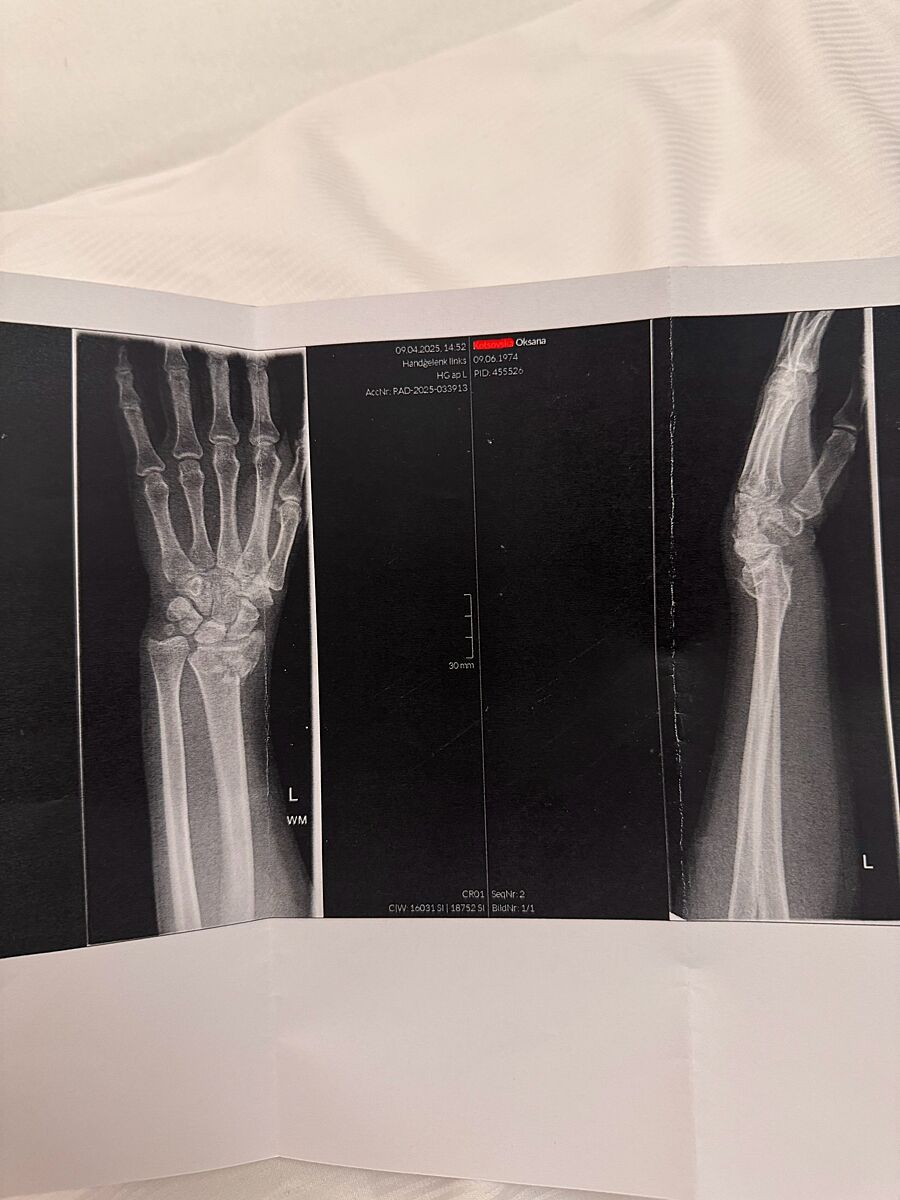

Сьогодні зламала руку

17

Сочувствую, все сможете когда заживет. Без смещения ?

Напено з зміщенням , я в Австіі на лижах , мови не знала

attached-photo

Когда со смещением ее складывают ( обычно это очень больно ) потом еще раз фоткают.

Ответ дляСоседка Маши

Мені так і робили . Перед тим обезболення кололи .

Ответ дляТоска в носках

Ви не за те переживаєте. Вам головне щоб правильно зрослося все, ще і зміщення.

Лікар сказав , що операцію треба буде робити по приїзду в Україну